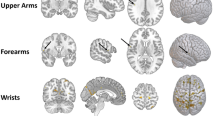

A MUCH debated question is whether sex differences exist in the functional organization of the brain for language1–4. A long-held hypothesis posits that language functions are more likely to be highly lateralized in males and to be represented in both cerebral hemispheres in females5,6, but attempts to demonstrate this have been inconclusive7–17. Here we use echo-planar functional magnetic resonance imaging18–21 to study 38 right-handed subjects (19 males and 19 females) during orthographic (letter recognition), phonological (rhyme) and semantic (semantic category) tasks. During phonological tasks, brain activation in males is lateralized to the left inferior frontal gyrus regions; in females the pattern of activation is very different, engaging more diffuse neural systems that involve both the left and right inferior frontal gyrus. Our data provide clear evidence for a sex difference in the functional organization of the brain for language and indicate that these variations exist at the level of phonological processing.